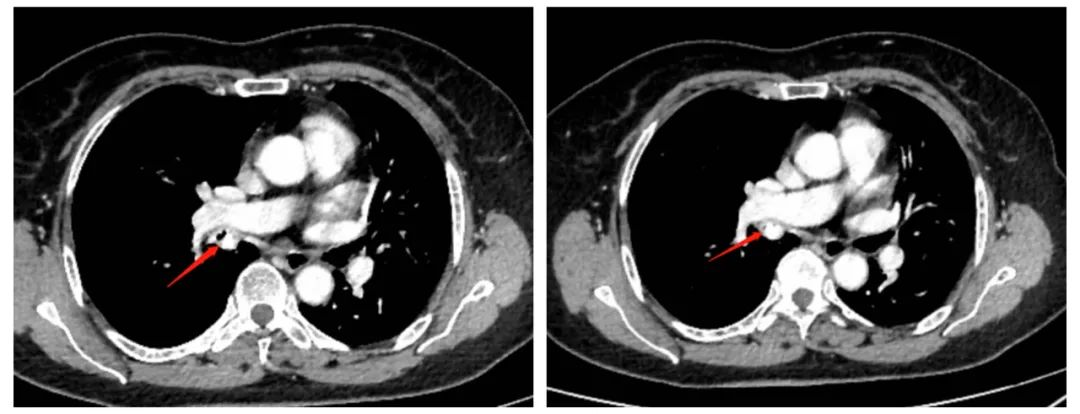

患者余阿姨,70岁,因“咳嗽、气促2月余”入住我院呼吸与危重症医学科。行胸部增强CT扫描示:右肺中、下叶支气管开口处结节状高密度异物存留并阻塞性肺气肿;气管镜示:右中间支气管可见一形状不规则物体,与周围气管粘膜有嵌顿,表面见黄白色坏死物覆盖,堵塞大部分管腔,4.2 mm气管镜无法通过,周围粘膜充血、水肿,触之即有出血;临床诊断右中间支气管异物并阻塞性肺气肿。

胸部箭头指向为支气管异物